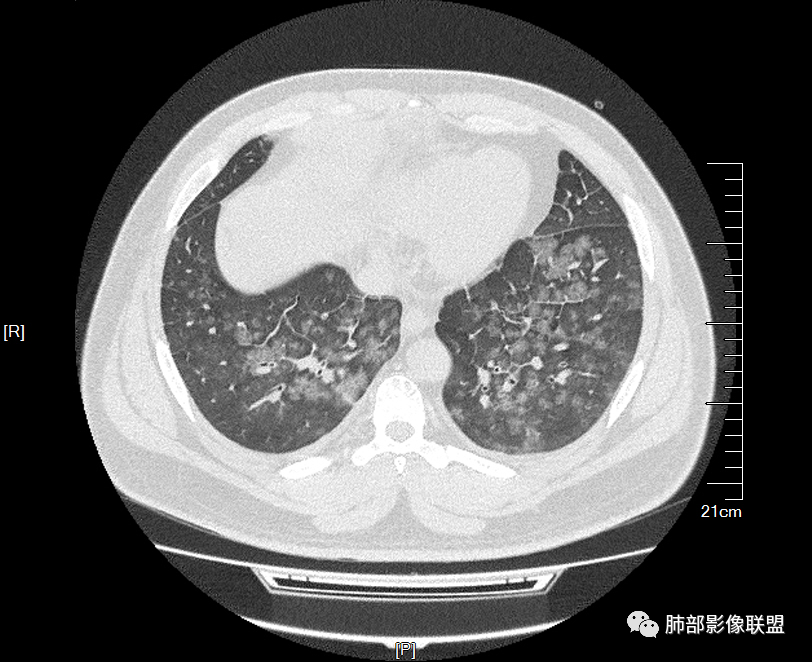

双肺多发腺泡结节及磨玻璃,小叶间隔增厚(大网格状),腺泡结节内及磨玻璃内可见细网格影(小叶内间隔增厚),影像表现符合肺泡出血改变,血肌酐升高,考虑肺肾综合征。鉴别肺水肿。

年轻男性,既往血肌酐升高,左足痛六天入院,有痛风及高血压病史。CT示双肺多发磨玻璃结节影,不规则,部分融合成团或片状,小叶间隔增厚,以双下肺为明显,叶间胸膜亦见增厚。考虑为1.Good-Pasture综合征。2.病毒性肺炎?3.肺水肿?

年轻男性,痛风史,高血压史,肌酐高,左足痛6天入院。胸CT:双肺多发弥漫性磨玻璃结节影,大小不一,部分融合,上中下肺都有,中内带多,胸膜下少。部分血管束略增粗,小叶内间隔、小叶间隔增厚,下肺明显,左室大。叶裂胸膜增厚。临床有痛风,左足痛6天,考虑:心衰、间质性肺水肿?弥漫性肺泡出血?鉴别:MPA,肺肾综合征,痛风结节等。

妞妞:

年轻男性,痛风,肌酐高,提示肾功能有损,两肺多发磨玻璃腺泡结节,小叶间隔增厚,双侧少许胸水,血管增粗,考虑肾性肺水肿,DAD,鉴别肺肾综合征,需要更多临床资料

32岁男性,左足痛入院。有痛风、肌酐升高、高血压病史。CT:两肺弥漫磨玻璃结节,小叶间隔增厚、小叶内间质增厚,两侧少量胸水。考虑:1.肺水肿;2.过敏性肺炎;3.肿瘤?

青年男性,双肺多发大小不等斑片状磨玻璃密度影,内见细网格影,并可见小叶间隔增厚,双侧胸腔少量积液,患者曾有血肌酐增高,提示曾有肾损害,并有痛风、高血压病史,考虑肺肾综合征,鉴别过敏性肺炎

小叶间隔增厚,无明显重力趋势

少量积液,脂肪肝

中轴间质增厚,小叶间隔增厚,小叶内间质增厚,部分重力作用,双侧对称,胸水,按理淋巴道回流受阻有

病例结果:肺水肿

我这个就是肺水肿

没有转移性钙化

肾性肺水肿症状可以不明显,尤其是这个病人已经有小叶间隔增厚,说明病程比较长,耐受较好了